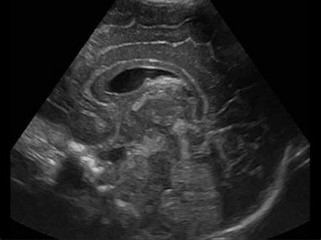

Pediatric sonography uses real time imaging with sound waves to diagnose conditions in organs and blood vessels. The sound waves allow the sonographer to clearly see many parts of the body, such as the abdomen, spine, hips, breasts, pelvis, scrotum, and thyroid. Pediatric ultrasound is a great diagnostic tool for children because there is no exposure to radiation and it is painless.